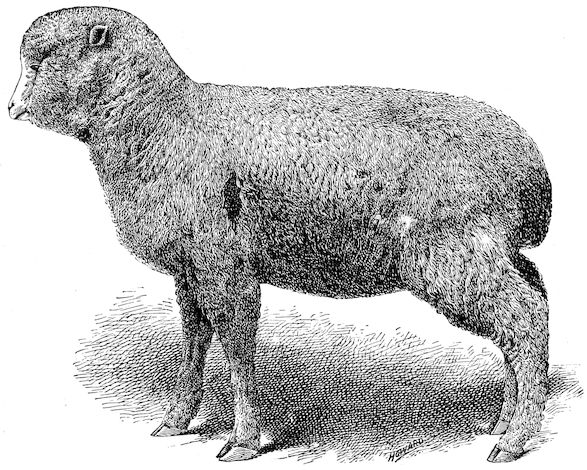

Fig. 1.—Rachitis in a young goat.